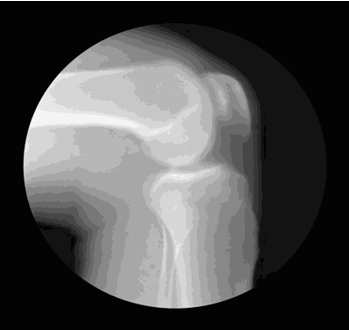

膝关节由股骨、胫骨和髌骨组成,股骨在上,胫骨在下,髌骨在表面。髌骨上连股四头肌,下连胫骨前侧,通过肌肉的收缩与放松来控制膝关节的屈伸。

这三块骨头彼此对接的关节处,覆盖着一层脆弱的软骨,软骨***怕的是长时间处于压力状态。当膝关节处于屈曲状态时,髌骨和股骨之间的压力会显著增大,股骨的后髁直接卡在胫骨上,也会导致股骨和胫骨之间的压力增大。

如果膝关节长期处于压力状态,软骨的抗磨损能力就会下降,就会像下图这样出现软骨退化、甚至剥脱,从而诱发骨关节炎。